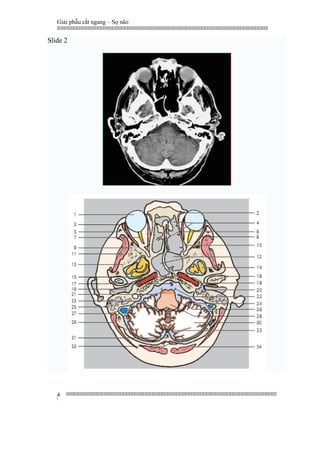

Slide 2

1 Eye ball

2 Superior oblique muscle

3 Lacrimal gland

4 Ethmoidal cells

5 Zygomatic bone

6 Medial rectus muscle

7 Optic nerve

8 Lateral rectus muscle of eyeball

9 Sphenoidal bone

10 Superior rectus muscle

11 Temporal muscle

12 Sphenoidal sinus

13 Temporal bone

14 Temporallobe (base)

15 Clivus

16 Temporomandibular joint and

head of mandible

17 Basilar artery

18 Internal carotid artery

19 External auditory meatus and

eardrum (tympanic membrane)

20 Tympanic cavity

21 Pons

22 Abducent nerve (VI)

23 Flocculus

24 Interior inferior cerebellar artery

25 Mastoid process and mastoid cells

26 Glossopharyngeal (IX) and agus (X)

nerves

27 Sigmoidsinus

28 Medullaoblongata (myelencephalon)

29 Spleniuscapitis muscle

30 Cerebellar hemisphere

31 Occipital bone

32 Occipital sinus

33 Rectuscapitis posterior minor muscle

34 Semispinaliscapitis muscle

1. Nhãn cầu

2. Cơ chéo trên

3. Tuyến lệ

4. Tế bào sàng

5. Cung gò má

6. Cơ thẳng trong

7. Thần kinh thị

8. Cơ thẳng ngoài nhãn cầu

9. Xương bướm

10. Cơ thẳng trên

11. Cơ thái dương

12 Xoang bướm

13. Xương thái dương

14. Đáy thuỳ thái dương

15. Mặt dốc (Khớp thân bướm mõm nền x chẩm)

16. Khớp thái dương hàm và lồi cầu xương

hàm dưới

17. Động mạch nền

18. Động mạch cảnh trong

19. Ống tai ngoài và màng nhĩ

(thuộc màng nhĩ)

20. Hòm nhĩ

21. Cầu não

22. Thần kinh vận nhãn ngoài (VI)

23. Thuỳ nhung tiểu não

24. Động mạch não dưới trong

25. Mỏm chũm và tế bào chũm

26. Thần kinh thiệt hầu (IX) và phế vị (X)

27. Xoang xích ma

28. Hành tuỷ (Hành não)

29. Cơ gối đầu

30. Bán cầu tiểu não

31. Xương chẩm

32. Xoang chẩm

33. Cơ thẳng bé sau

34. Cơ bán gai